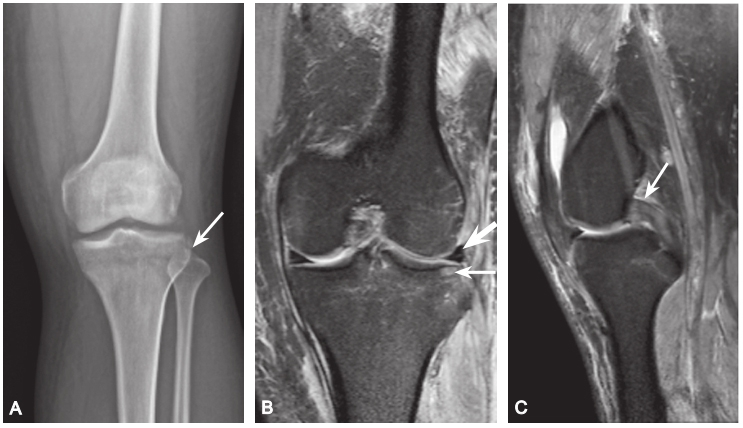

(5)Segond、反 Segond 骨折

Segond 骨折:胫骨平台前外侧撕脱骨折,多因为下肢过度内翻加内旋暴力所致,常伴有前交叉韧带、内外侧半月板的损伤。

A. 膝关节 X 线前后位片,胫骨平台外侧缘撕脱椭圆形小碎骨片,长轴平行于胫骨,见侧囊征(箭头);B. 同一患者 MRI 冠状位 PDWI SPAIR 显示胫骨平台外侧缘撕脱骨折(细箭头),内外侧半月板内横形高信号,提示损伤(粗箭头);C. 矢状位 PDWI SPAIR 中间层面 PCL 显示肿胀,信号不均,提示 PCL 水肿,呈轻度损伤(箭头)

反Segond 骨折:在膝关节X 线前后位或 CT、MRI 冠状位显示,表现为胫骨平台内侧缘撕脱性骨折。碎骨片常向外移位,可伴后交叉韧带损伤;MRI 可观察膝关节前交叉韧带、内侧副韧带和内侧半月板损伤情况。